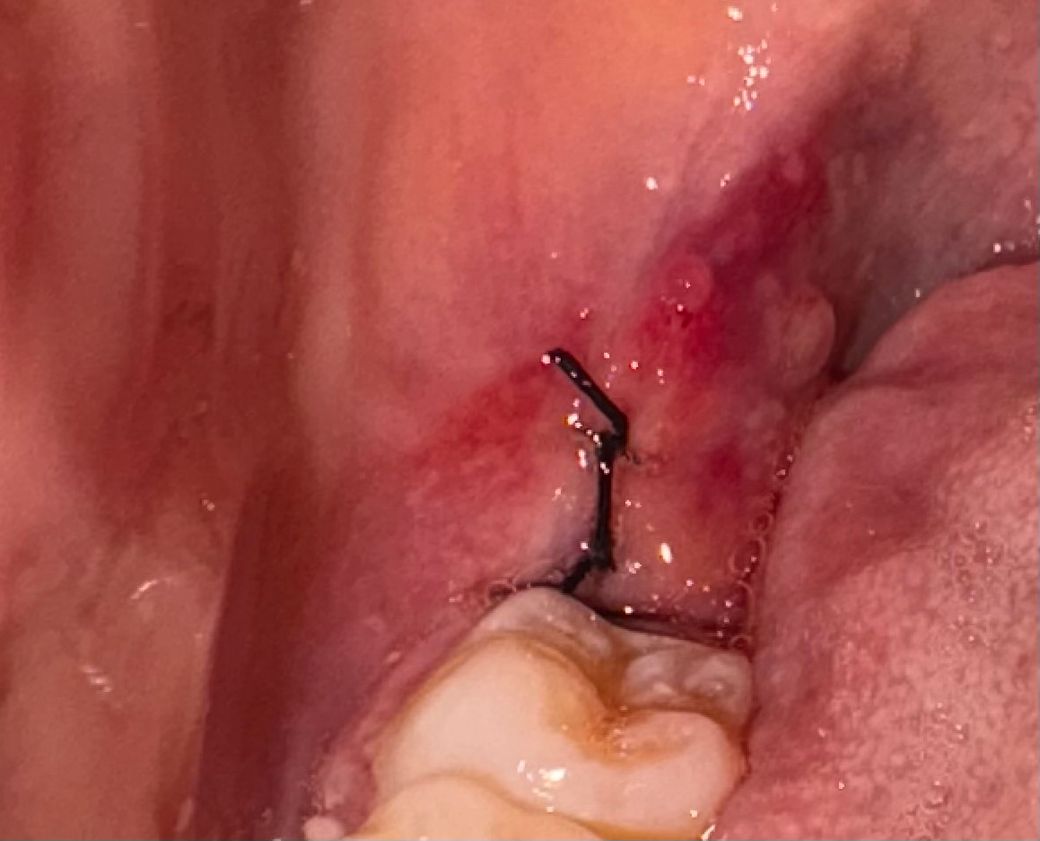

사랑니 발치 후 실밥 뒤에 저게 뭔가요??

사랑니 발치 후에 앞 어금니쪽에 혈병이 생겼는데 혈병이 그런지 자다 일어나니까 없어졌거든요....

오늘 아침에 다시 봐보니까 사랑니 실밥 뒤에 저런 젤리? 같은 것들이 있는데 그냥 부은 건가요 혈병인 건가요??

• 2번 째 사진

발치를 하면서 잇몸이 눌려서 생긴 물집같은겁니다. 크게 걱정은 안하셔도 될것같습니다.

발치 후 발치 부위 단순 염증이 생긴 것 같습니다 양치 등 구강위생관리 잘해주시면 사라질 것 같습니다